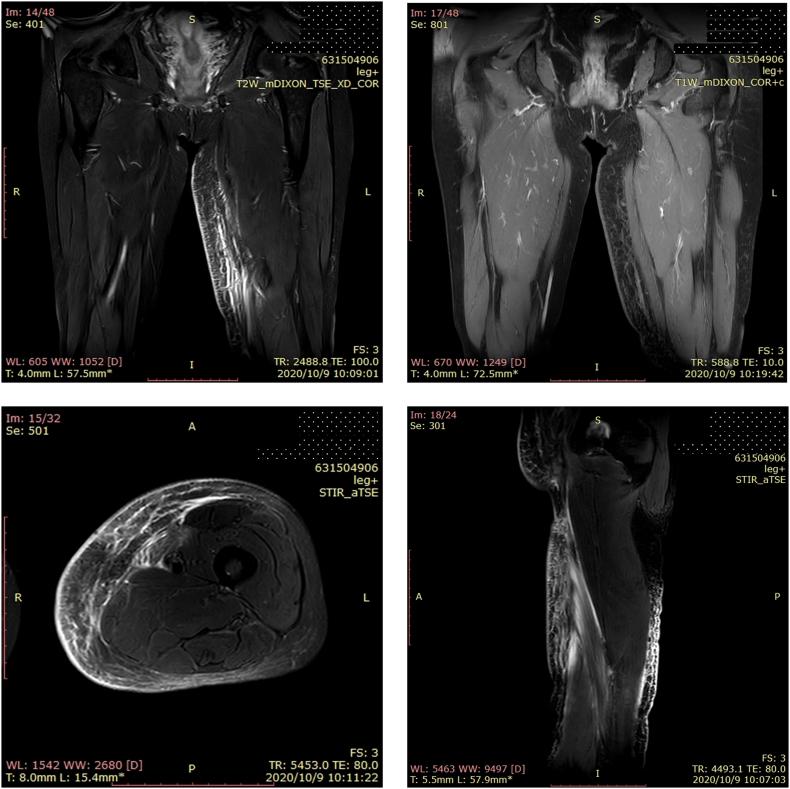

The aim of lymph node dissection for melanoma patients is to prevent metastasis. However, this procedure is accompanied by a long-term and impaired life-quality complication called . This condition involves long-term lower limb swelling, which causes discomfort and impaired function, and affects patients both physically and psychologically. Herein, we conducted a retrospective cohort study at a single center to investigate the risk factors associated with lower extremity lymphedema after inguinal lymphadenectomy.

The follow-up results from 85 melanoma patients who underwent inguinal lymphadenectomy were analyzed. Multivariate logistic regression analysis showed that number of lymph nodes removed ≥ 10 was the significant risk factor for postoperative lower extremity lymphedema (odds ratio = 6.468, P = .042, 95% confidence interval: 1.069 to 39.147). Moreover, 8 (100%) patients in the lower extremity lymphedema group and 32 (53.3%) patients in the normal group were female, which indicated that female patients might be more susceptible to postoperative lower extremity lymphedema (P = .012).

Our study found that number of inguinal lymph nodes removed ≥ 10 was associated with a significantly higher incidence of lower extremity lymphedema with a 6.5-fold increased risk in melanoma patients. Also, female patients were more likely to develop lower extremity lymphedema after inguinal lymphadenectomy.